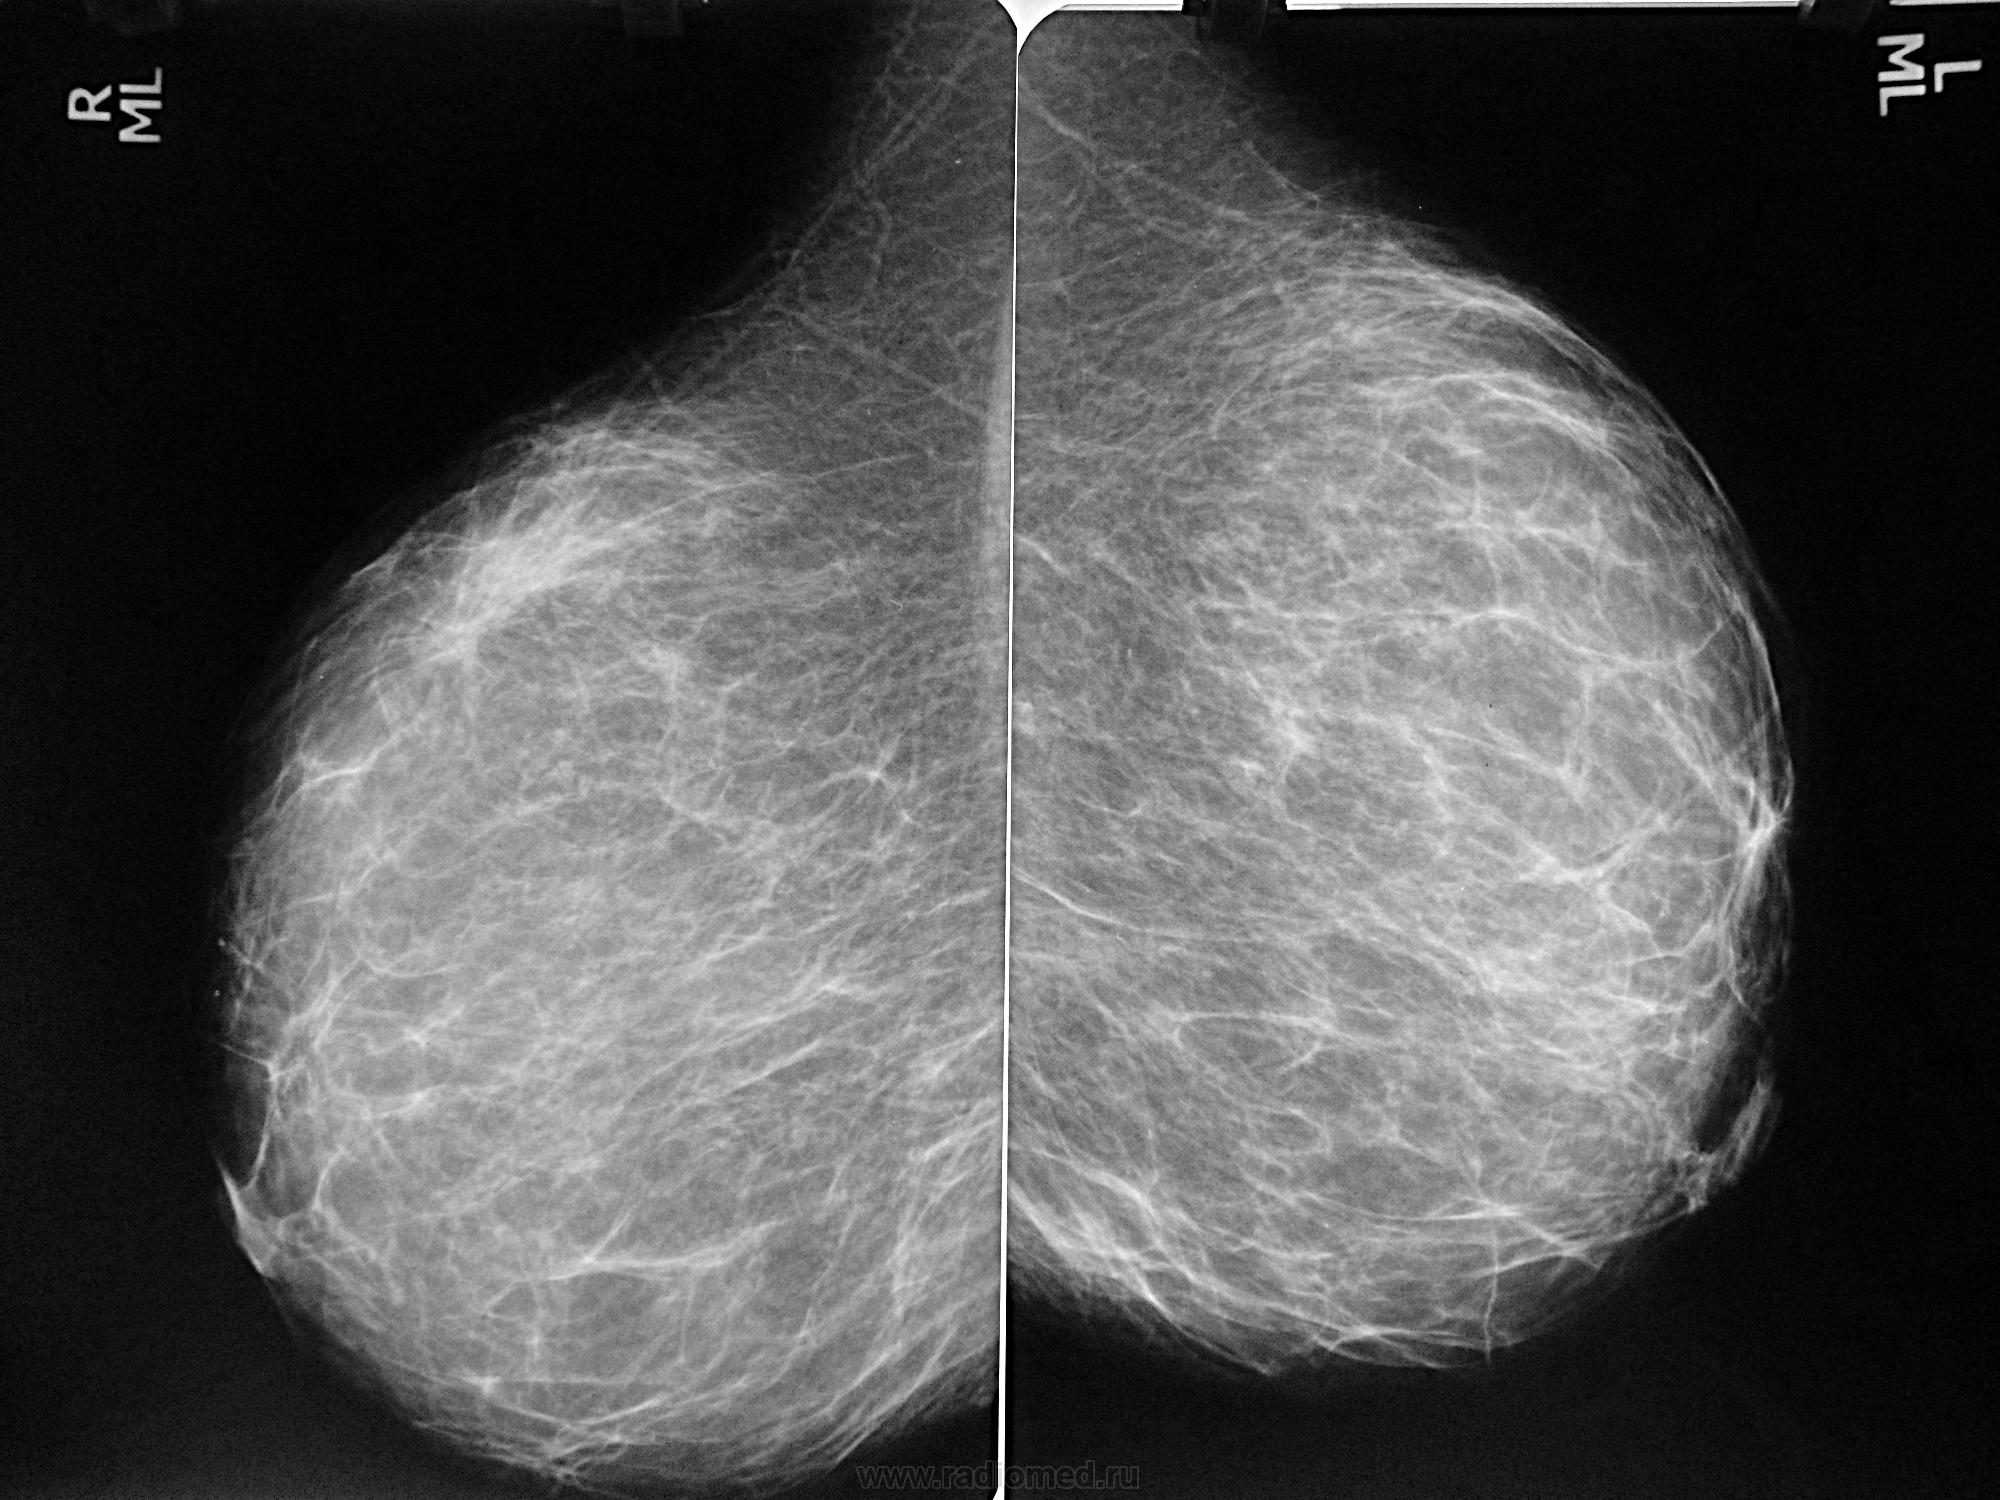

Феномен гипердиагностики в маммографии: примеры и иллюстрации

Раздел: Образы вокруг